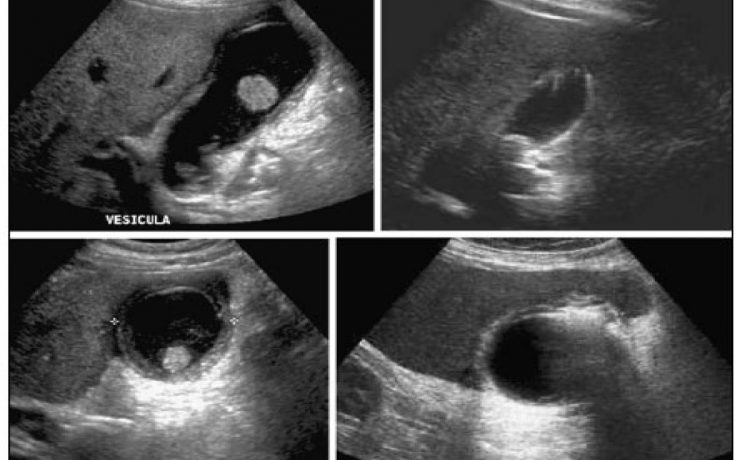

El presente artículo tuvo el objetivo principal analizar la funcion sexual en mujeres portadoras de miomas durante un año, tomando en cuenta el no deseo sexual, la falta de excitación, la falta de orgasmo, presencia de dispareunia y dolor pélvico. El mioma es el tumor solido más frecuente en la